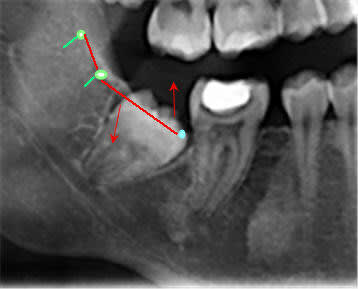

Si ce système n'est pas réalisable, c'est tout simplement parce qu'on ne met jamais de vis en lingual au niveau des molaires inférieures, essentiellement à cause de la langue.

Le plus simple est d'en utiliser une courte qu'on placera dans le bord antérieur de la branche montante après l'avoir enfilée dans l'anneau d'une ligature qui émergera, elle, en distal de la molaire. Voir planche photo jointe.

Daniel